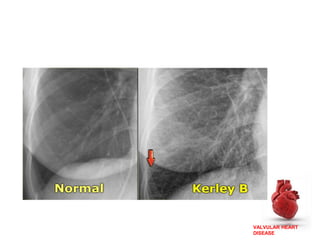

• ECG-Tall peaked P wave in lead 2,upright in V1

• CXR-

1. Straightening of upper left cardiac border

2. Prominence of main pulmonary arteries

3. Dilatation of upper lobe pulmonary veins

4. Postr displacement of esophagus by enlarged LA

5. Kerley-B lines-Fine, dense, opaque, horizontal lines

most prominent in lower&mid zones